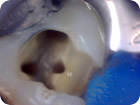

Podemos disponibilizar os dados do tratamento em um relatório de atendimento, que contém fotos, radiografias e informações sobre o que foi realizado.

Tratamento Endodôntico

Tratamento Endodôntico 1

Tratamento Endodôntico 2

Tratamento Endodôntico 3

Tratamento Endodôntico 4